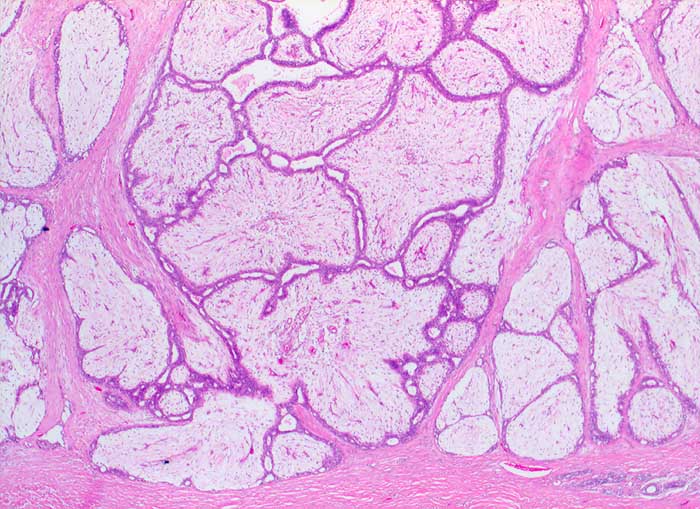

Biphasischer scharf begrenzter lobulierter Tumor bestehend aus verzweigten epithelial ausgekleideten Gangstrukturen, die von einem zellarmen ödematösen Stroma komprimiert werden.

Histologische Diagnose: Fibroadenom mit ausgeprägtem Stromaödem

Zytologische Diagnose: Fibroadenom / phylloider Tumor